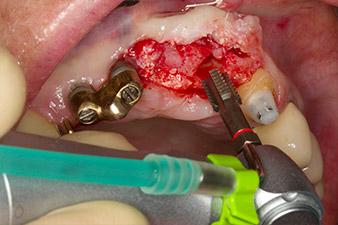

Following primary healing, the soft tissues were shaped using the basally lined bridge. Two months later the site was exposed by a slightly palatal alveolar ridge incision (Fig 2). The dimensions of the alveolar bone proved to be sufficient at position 22. Figures 2 and 4 show the preparation of the implant bed, the tapping and the implantation using Implantmed.